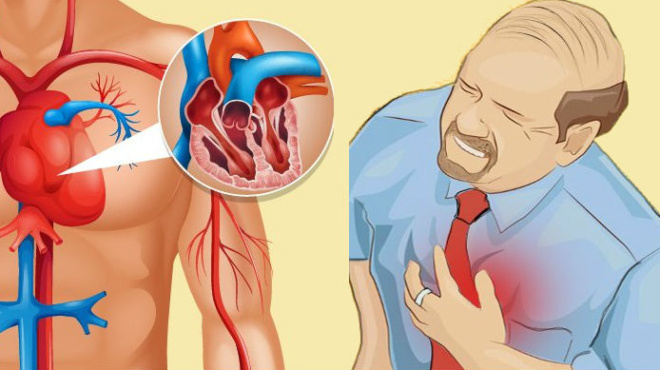

Αρτηρίες όταν είναι φραγμένες σημαίνει ότι έχουν συσσωρευτεί στα τοιχώματά τους λιπαρές ουσίες. Η κατάσταση για τον ασθενή χαρακτηρίζεται ως επικίνδυνη. Είναι “σιωπηλή” και δεν προκαλεί εμφανή σημάδια και συμπτώματα. Συχνά περνά απαρατήρητη μέχρι να προκαλέσει επιπλοκές όπως ένα έμφραγμα ή ένα εγκεφαλικό επεισόδιο.

Χιλιάδες άνθρωποι κάθε χρόνο παθαίνουν έμφραγμα του μυοκαρδίου ή πεθαίνουν από στεφανιαία καρδιακή νόσο.

Βασική αιτία είναι φυσικά οι φραγμένες αρτηρίες που εμποδίζουν τη ροή του αίματος και κουράζουν την καρδιά.

Δείτε 4 βασικά σημάδια που δείχνουν ότι έχετε σοβαρό πρόβλημα απόφραξης στις αρτηρίες και πρέπει να ενημερώσετε άμεσα το γιατρό σας: